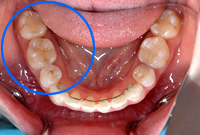

治療前

治療後

治療説明:銀の詰物をセラミックに変えた症例

治療期間:2週間

治療の料金:66,000円(税込)